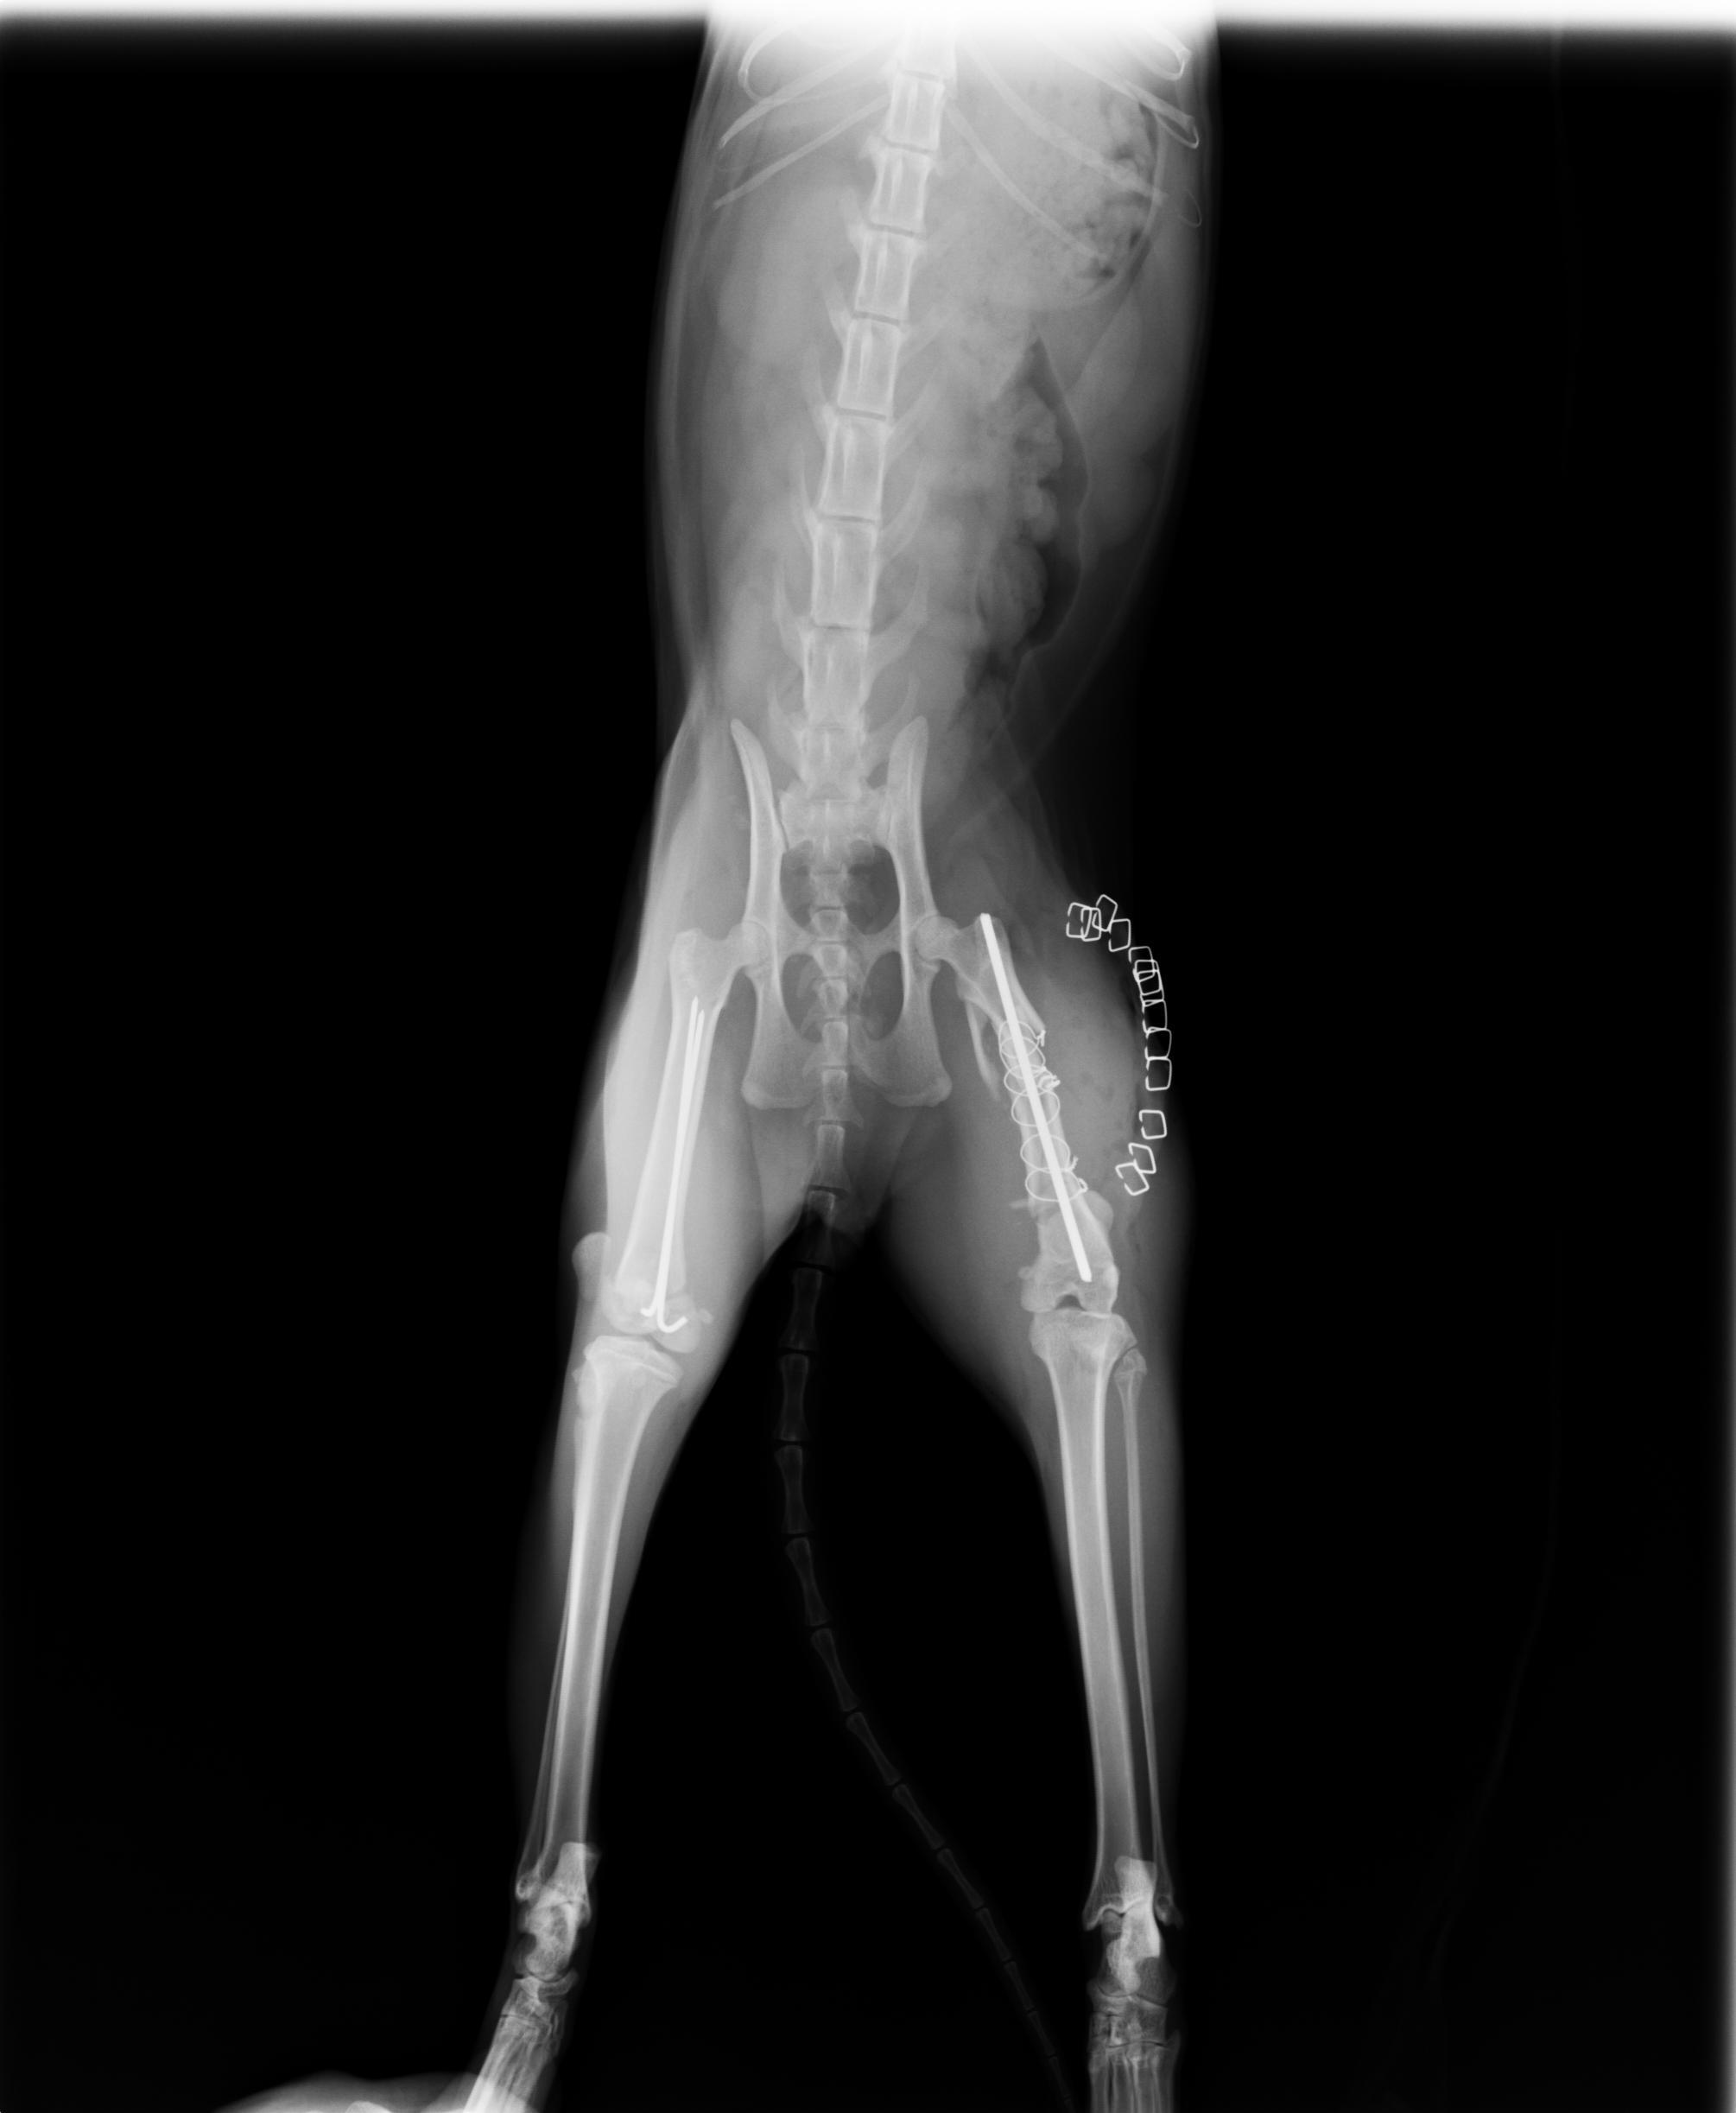

主題: 車禍後左腳粉碎性骨折及後右腳骨折 申請者姓名: 許桂菱 花色: 申請日期: 2013-04-01 00:14:01 申請者部落格: 申請者臉書網址: 所在縣市/合作醫院: 台中市/春天動物醫院 治療費用: 25100元 需求人數: 26人 已結案 (2013-06-27 14:19:18) 報名人員: 小娃(已付款)、nini(已付款)、陳嘉芸(已付款)、Hui Mei Chen(已付款)、Ann Cat(已付款)、蔡秀芳(已付款)、高小玉(已付款)、Irene Chu(已付款)、Huei Wen Chuang(已付款)、Maureen Huang(已付款)、Winnie Chen(已付款)、chiawei(已付款)、May Ho(已付款)、潘逸群(已付款)、BonnieL(已付款)、Richie Hsu、Chenyu Chang(已付款)、Richie Hsu、Yuki Natumei(已付款)、Ou Han x2(已付款)、Kiki Liang(已付款)、Ching-fang Shaw(已付款)、Cathy Chang(已付款)、胡嘟嘟(已付款)、胡嘟嘟(已付款)、Claire Hoi(已付款)、Judy媽(已付款)、 候補人員: 動物病情說明: 原在鹿港市場的大有街且已TNR之公浪貓,因車禍造成後左腳粉碎性骨折及後右腳骨折而無法行走!醫院先進行右腳骨折手術,於一星期後進行左腳粉碎性骨折的拼接手術,右腳於兩星期恢復良好且能行走,但貓咪雖受傷對左腳傷口卻想盡辦法去舔開,造成傷口癒合時間拉長,經過一個月後,左腳傷口癒合情況良好!

動物近況說明: 左腳因施力仍會疼痛,目前暫時在鹿港大有街原生長地之居民空屋休養中途,並進行送養中!